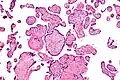

VUE can be of 2 types, low grade chronic villitis or high grade chronic villitis. Low grade chronic villitis involves less than 10 villi containing lymphocytes. Low grade chronic villitis can be either focal or multifocal. Focal has involved villi on only one glass slide, while multifocal has involved villi on at least two slides. High grade chronic villitis has more than 10 inflamed villi per focus. High grade chronic villitis is differentiated into diffuse and patchy. The term patchy is used if less than 30% of distal villi are involved. The term diffuse is used if more than 30% of distal villi are involved.

VUE has 2 prominent distinct patterns. Approximately 50% of the cases only involve the distal villi (mature intermediate and terminal villi) and do not involve the proximal stem villi, the anchoring villi embedded in the basal plate, and the chorionic plate. The second most common pattern (roughly 30% of VUE cases) involves the proximal stem villi (and possibly the chorionic plate) and the distal villi usually. This type of VUE is linked with foetal vascular obtrusive lesions (Obliterative Foetal Vasculopathy).[1][16]

Histomorphologically, VUE is characterized by a lymphocytic infiltrate of the chorionic villi without a demonstrable cause. Plasma cells should be absent; the presence of plasma cells suggests an infective etiology, e.g. CMV infection.